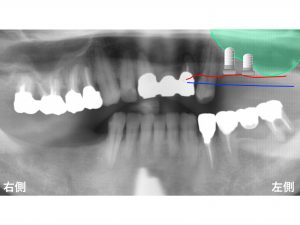

以下の赤線 が現在の骨吸収した位置です。

さらに問題となったのが、

上顎洞 の存在です。

上顎洞とは、

上顎の奥歯の上方にある空洞のことです。

この空洞(上顎洞)の位置や大きさ等には、

個人差が大きくありますが、

今回のケースの患者様の場合、

かなり低い位置(下方に下がっている)でした。

上顎洞という空洞を緑色 で表示します。

この緑の領域 は全て空洞です。

骨吸収の状態と上顎洞を合わせたのが以下です。

手前の欠損部でも

骨の高さは非常に少ないです。

奥歯に関しては、

インプラントを埋め込むための骨の高さが

ほとんどない状態です。